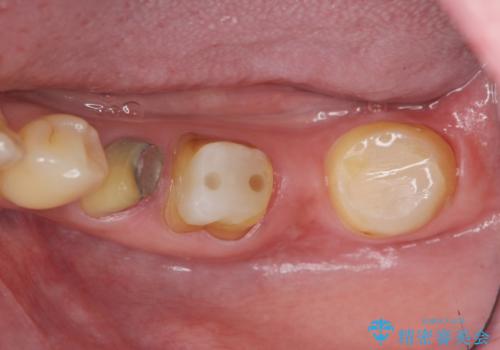

抜歯後、インプラントを用いて咬合機能を回復すると共に周囲に強固な角化歯肉を移植することによりより長期にわたり安定したインプラント周囲環境となるよう治療を計画します。

インプラント周囲の角化歯肉が存在することにより、歯ブラシがしやすくなりインプラントにトラブルが起きる確率を減らしより長期的な予後を望むことができます。